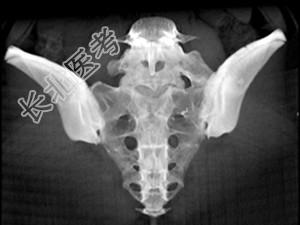

- 单项选择题男,35岁, 下腰部痛,L4-5棘突旁有明显压痛, 结合图像,最可能的诊断是 ( )

C、腰椎骶化

D、骶椎腰化